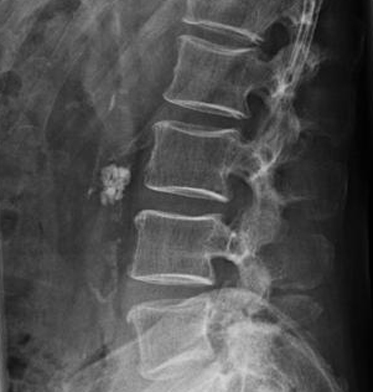

Image

radiologique ASP d'une calcul de la vesicule

biliaire cholesterolique |

Lithiase vesicule biliaire multiple se forment par la saturation de la bile en cholestérol et

par la

précipitation les cristaux de cholestérol  .

Image de calcul cholesterolique de la vesicule

biliaire |